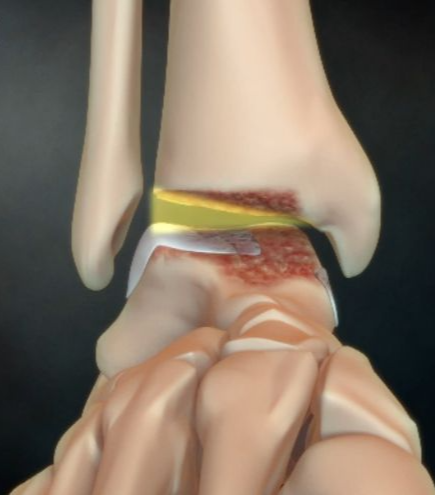

발목연골은 위 그림에서 거골과 연골 사이에 있다. 그 화면은 그냥 지나가서 말로 설명.

연골이 이렇게 닳는다.

무리한 운동! 인공관절수술을 부른다!

사례환자) 장년과 노년에 빨리걷기 운동이 좋다고 해서 너무 많이 했더니.. 퇴행성 발목 관절염

인공관절수술해야.

발목 인공관절치환술

원래 관절이 붙은 뼈끝을 관절과 함께 잘라내고 환자의 몸에 맞는 인공관절을 박아넣는 수술이기 때문에 회복하는 데도 오래 걸린다.

이렇게 원래 뼈를 잘라내는 치료다. 그리고 요즘은 인공관절 소재기술이 좋아져서 10년 정도로 본다고. 그래서 수술을 한 번만 받겠다면 되도록 늦게 받는 게 좋다.